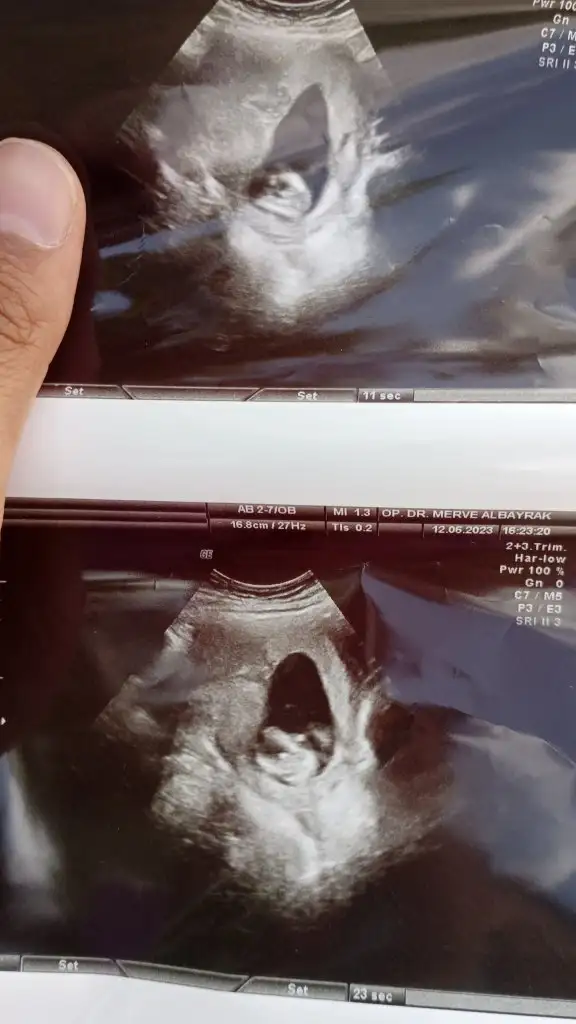

Evet canm ilkten bacaklar kapalıydı göstermedi yarım saat sonra tekrar bakti geçen haftada mınık bisey vardı yıne aynı 14+1 ı'm net brsy demedi çıkıntıda büyüme yok hayla ufak dedı yanılma da olabilir hafta tekrar bakacak çok merak ediyorum

• IMG-20230612-WA0045.webp

IMG-20230612-WA0045.webp

26,9 KB · Görüntüleme: 103

• IMG-20230612-WA0042.webp

IMG-20230612-WA0042.webp

27,2 KB · Görüntüleme: 102

Sen neye benzettin